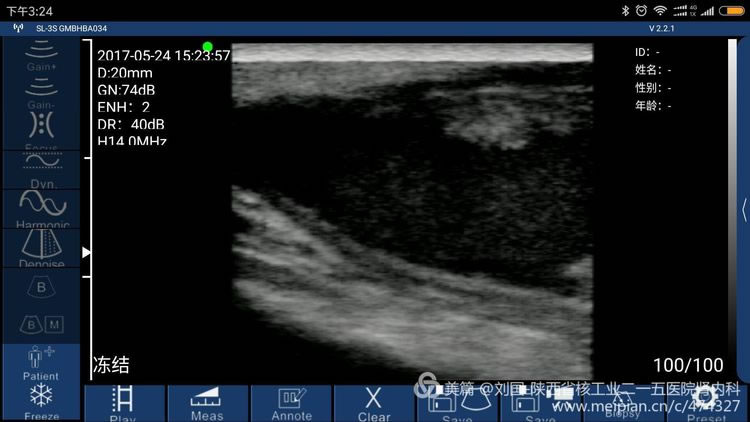

索诺星无线超声所查的结果,显示器是我的小米max。

索诺星无线超声检查的头静脉情况,显示器是我的小米max。